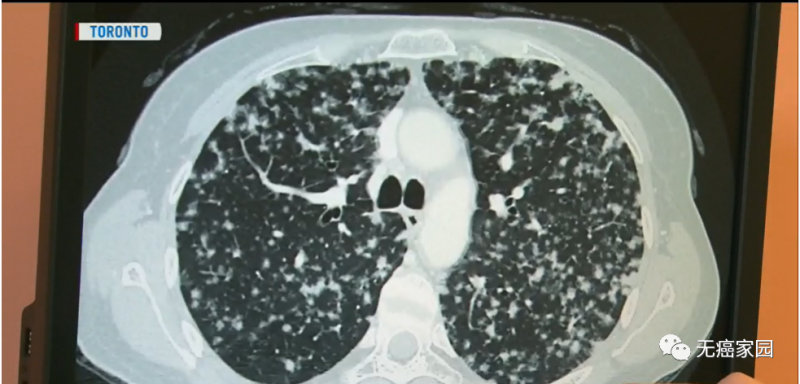

就在她接受一系列治疗的2年后,得到了更加毁灭性的消息:癌症已经扩散到她的另外一个肺部,无法进行手术治疗,她的病情也好似画上了休止符。

就在7年前,塞拉托克服重重困难,采用了靶向治疗的新型疗法。这种疗法是癌症医学的一种新趋势,超级幸存者的寿命比以往任何时候都要长。

以塞拉托为例,她每天只服用两片劳拉替尼的靶向药进行治疗。之所以能够服用这种抗癌新药,全都源于她的肿瘤发生了ALK(间变性淋巴瘤激酶)基因突变,这种突变会发生在3%~5%的肺癌病例中。

虽然生活方式很奇怪,需要每三周进行一次体检,甚至每隔一周扫描一次,但是7年后,她的生活状态很好,达到了与肺癌共存!她正在考虑重返工作岗位。她与其他被诊断出患有肺癌的患者交谈,并结识了她的伴侣帕特里克并与之结婚。